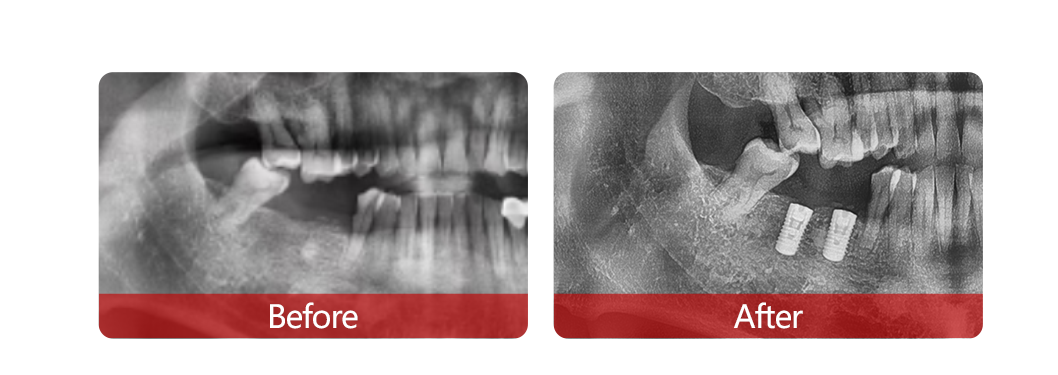

活動現場,近百名缺牙市民和成都電視臺等媒體一道,零距離“圍觀”60歲的鮑叔叔僅用20分鐘落齒重生2顆新牙的全過程,植樹節當日“種牙得牙”的夢想成真。